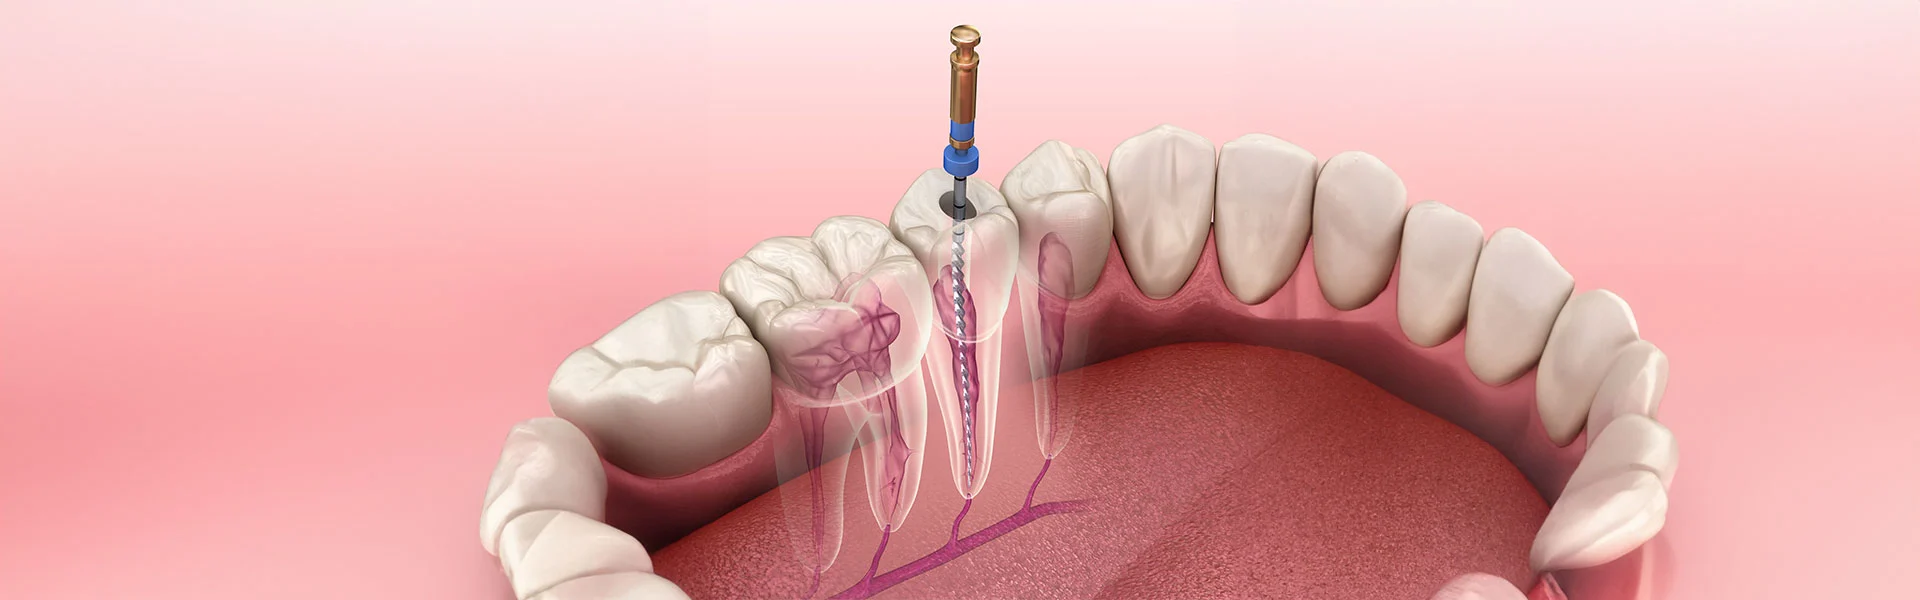

রুট ক্যানেল ট্রিটমেন্ট একটি আধুনিক ও কার্যকর ডেন্টাল চিকিৎসা। দাঁতের ভেতরের সংক্রমিত পাল্প বা নার্ভ টিস্যু সরিয়ে জীবাণুমুক্ত করার পর সেই অংশ সিল করে দেওয়া হয়। ফলে ভবিষ্যতে আর সংক্রমণ হয় না এবং দাঁতটি দীর্ঘ সময় ধরে সুস্থ থাকে।

ভিআইপি ডেন্টাল জোন দিচ্ছে সাশ্রয়ী মূল্যে বিশ্বমানের রুট ক্যানেল ট্রিটমেন্ট। অভিজ্ঞ ও প্রশিক্ষিত ডেন্টাল সার্জনের পাশাপাশি আমাদের রয়েছে আধুনিক রোটারি রুট ক্যানেল টেকনোলজি। পরিচ্ছন্ন ও আরামদায়ক পরিবেশে সম্পূর্ণ ব্যথাহীনভাবে রুট ক্যানেল ট্রিটমেন্ট পেতে আজই অ্যাপয়েন্টমেন্ট নিন।

১। ম্যানুয়াল রুট ক্যানেল চিকিৎসা ৩-৪ বারে সম্পন্ন হয়।